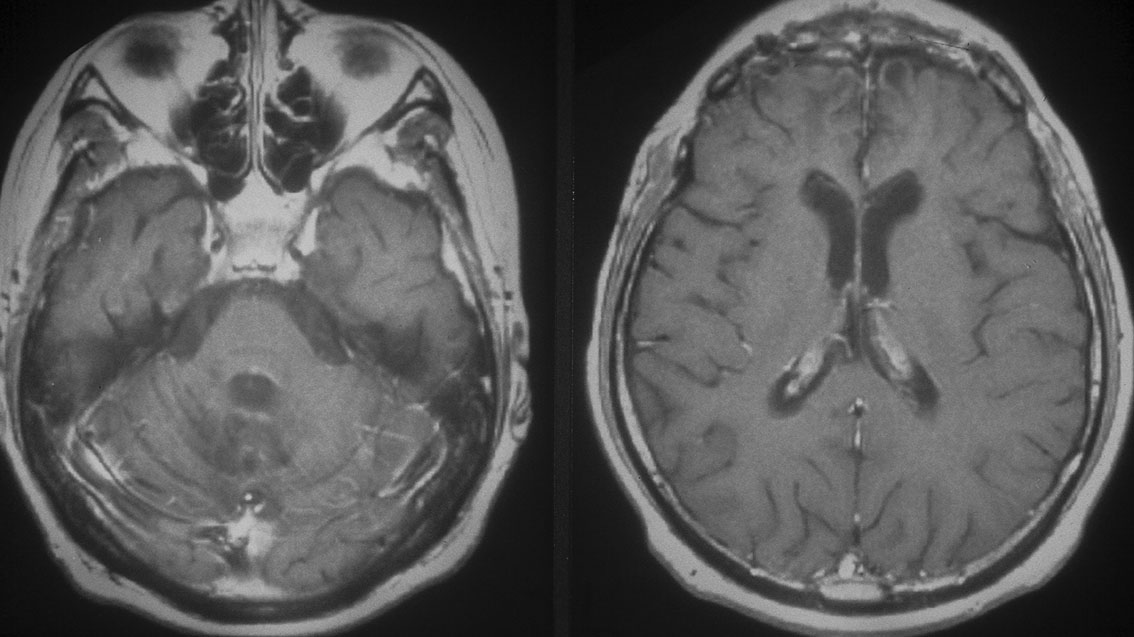

11歳(1977年)で発症して放射線治療を受け,21歳(1987年)で再発しました。側脳室の前角にガドリニウム増強される典型的なgerminomaの再発像がみれます。脳表にも脊髄にも髄液播種はありませんでした。

CDDP/VP-16化学療法で腫瘍は消失し,放射線治療を加えました。

2度目の再発です。側脳室の壁に再発したので,また化学療法をしましたら,右の画像のようにきれいに消えました。この時点でも髄液吸収障害性水頭症にも閉塞性水頭症にもなっていません。

3度目の再発です。また脳室の壁から再発しました。化学療法で腫瘍はまた消失しました。その後も維持化学療法を行ったのですが,脳室内再発が止められず,第4脳室底部の腫瘍が延髄に浸潤して死亡しました。

最後まで水頭症はありません。